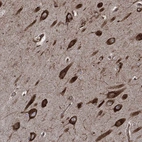

Immunohistochemical staining of human hippocampus shows strong cytoplasmic positivity in neuronal cells and glial cells.